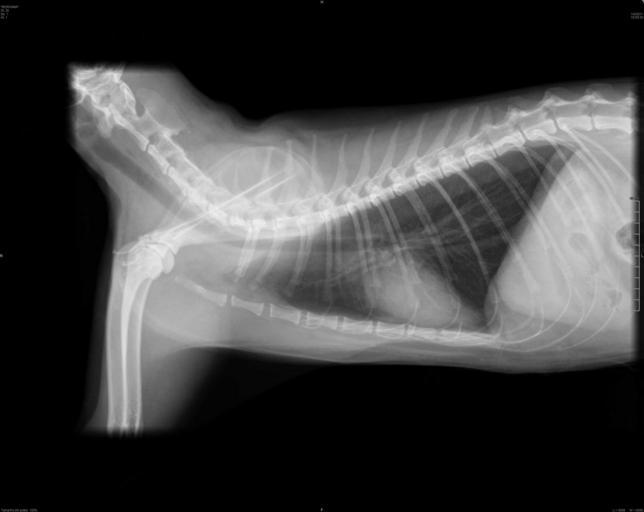

MAKE A MEME View Large Image Radiografia-lateral-gato.jpg en Lateral chest radiograph of a female domestic cat pt Radiografia lateral do tórax de um gato doméstico fêmea own AurelioAHeckert 1/4/2011 REGIÃO RADIOGRAFADA Tórax INCIDÊNCIA Latero-lateral LAUDO ...

Keywords: Radiografia-lateral-gato.jpg en Lateral chest radiograph of a female domestic cat pt Radiografia lateral do tórax de um gato doméstico fêmea own AurelioAHeckert 1/4/2011 REGIÃO RADIOGRAFADA Tórax INCIDÊNCIA Latero-lateral LAUDO RADIOGRÁFICO Silhueta cardíaca dentro dos parâmetros radiográficos normais Silhuta pulmonar apresentando calcificação de parede bronquial processo senil Não há evidências de imagens radiográficas sugestivas de metástase pulmonar nas incidências em estudo Traquéia com calibre conservado em toda sua extensão Veia cava caudal e aorta descendente sem alterações radiográficas Cat bones Veterinary radiology